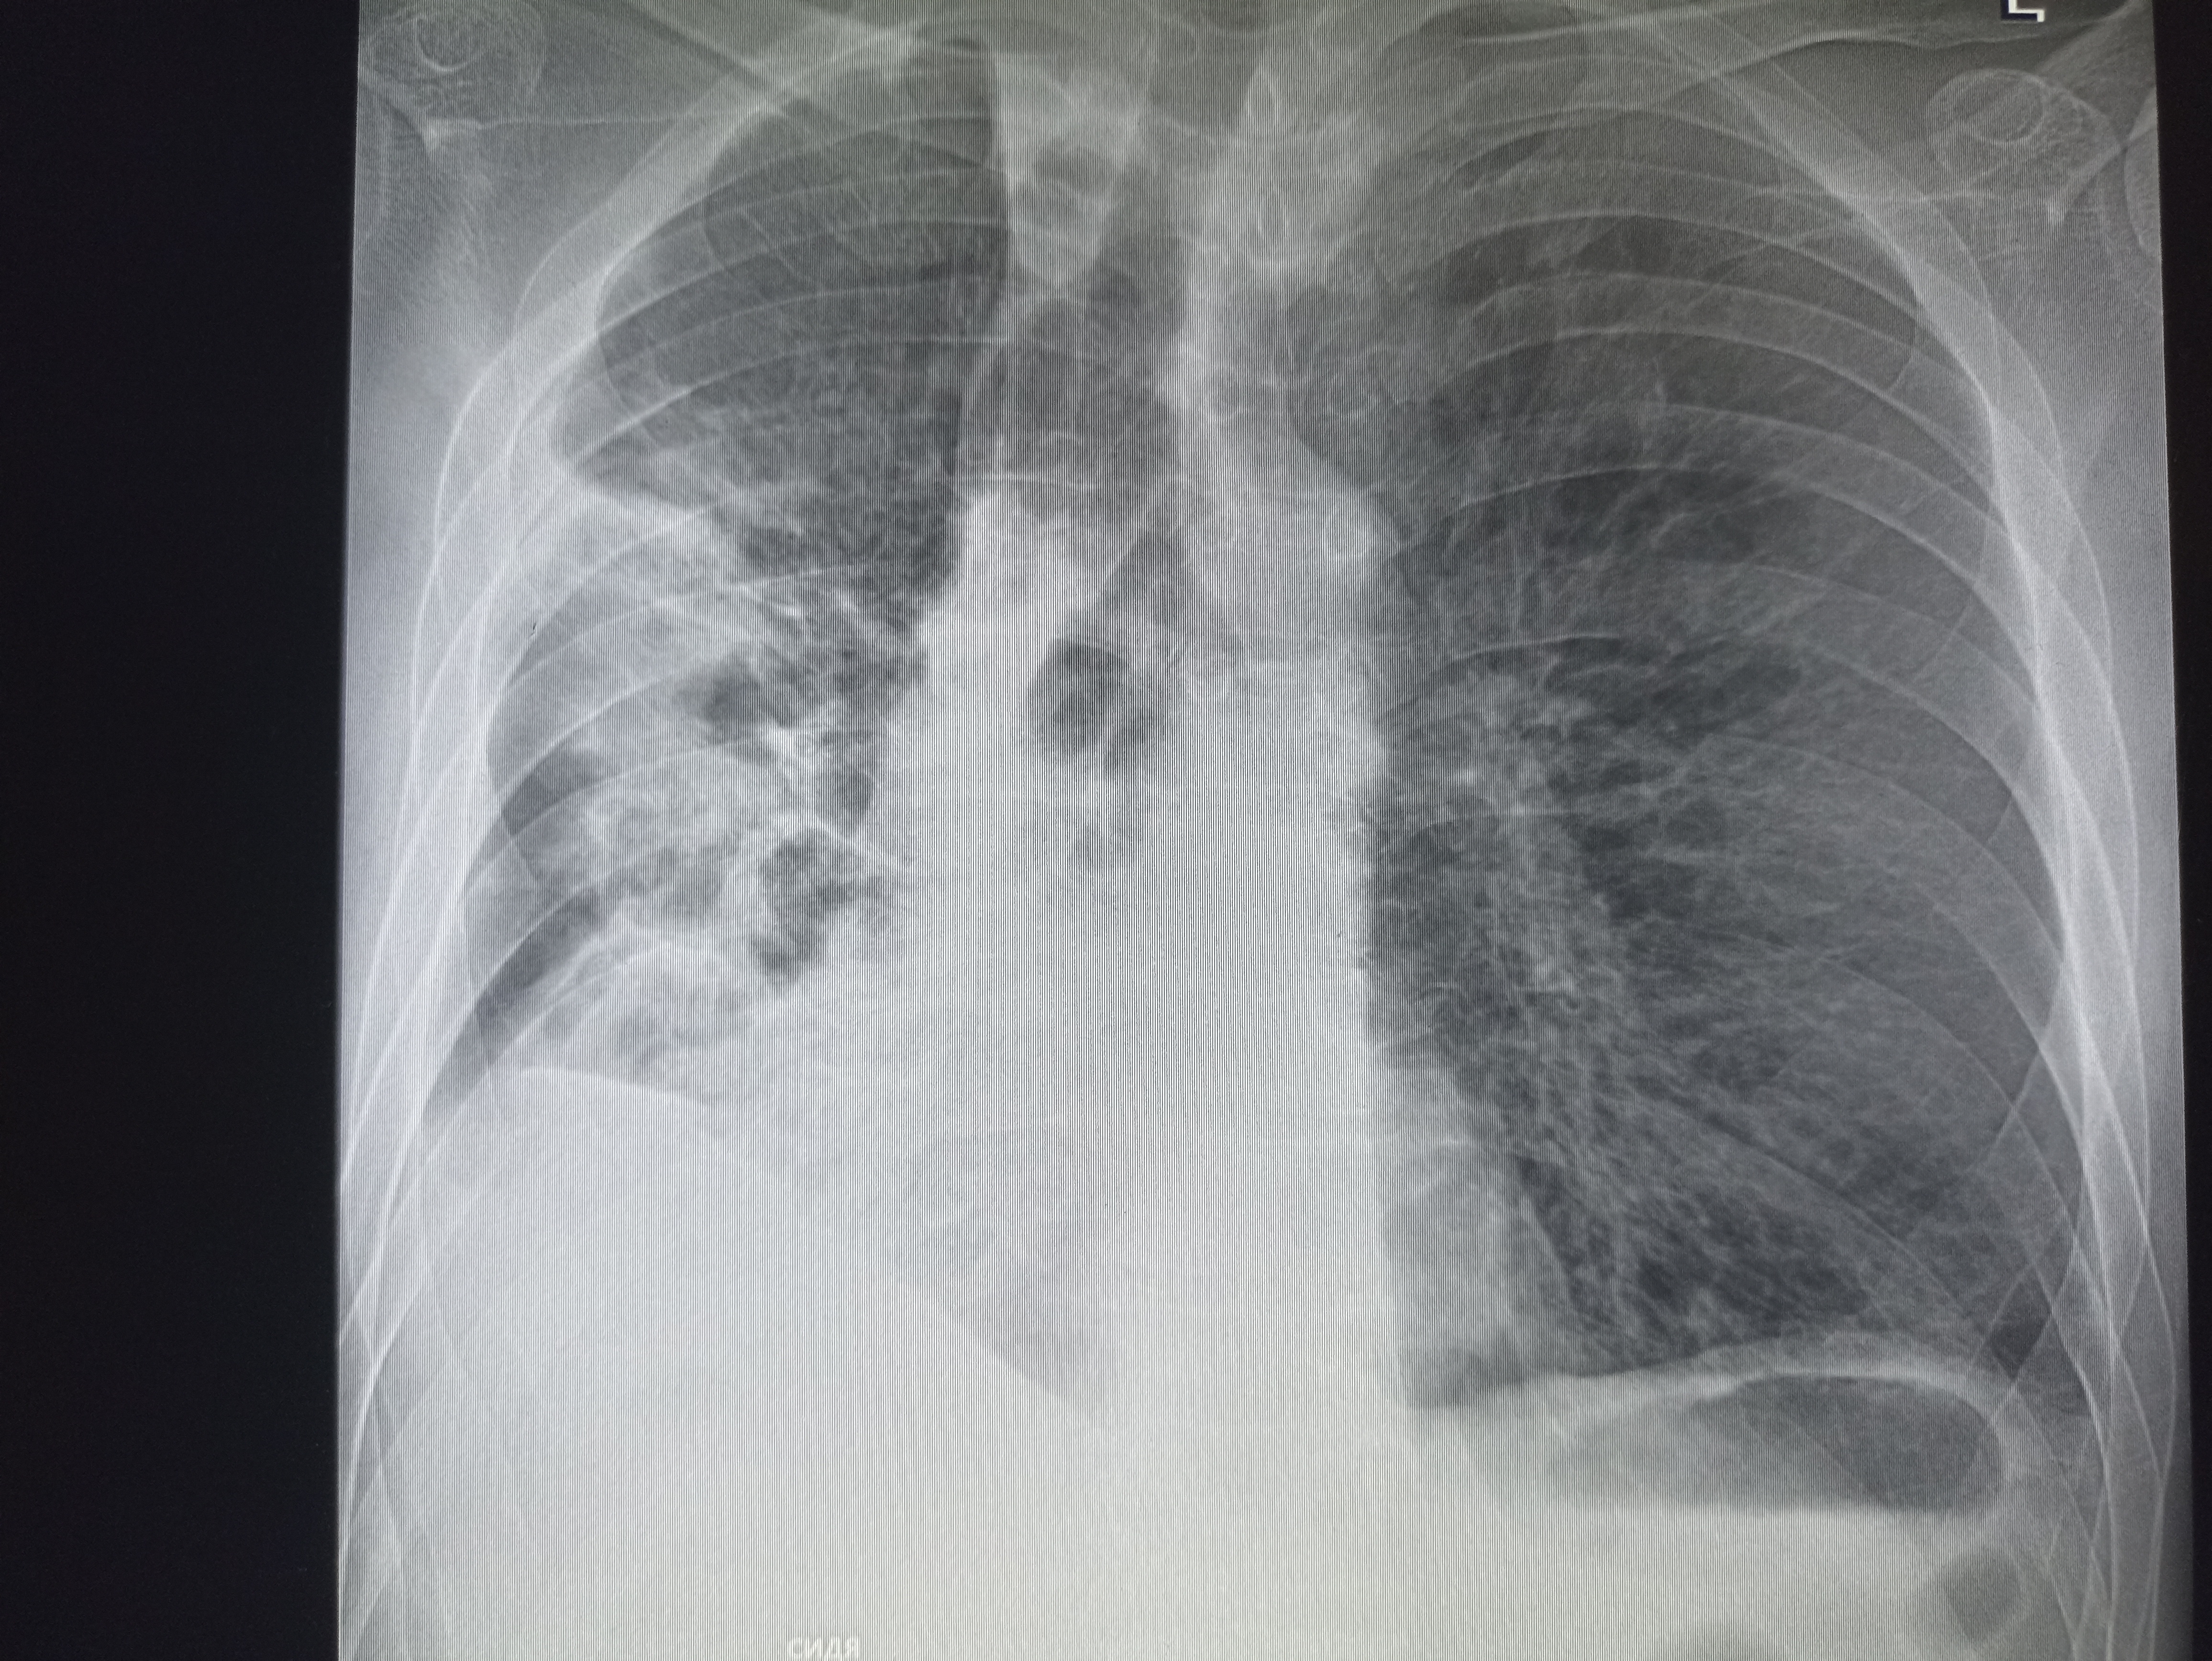

IMG20251009125406.jpg

Где пиздецома?

>>325599559

Типичный рак легких

Аноним 16/10/25 Чтв 08:58:28 #14 №325599625

вообще, как клинический диагноз. я бы предположил тубик, тут и затемнения есть и в корнях кругленькие л/у? и какая то диссеминация справа.

Там он был, это пост туб изменения снята с учета.